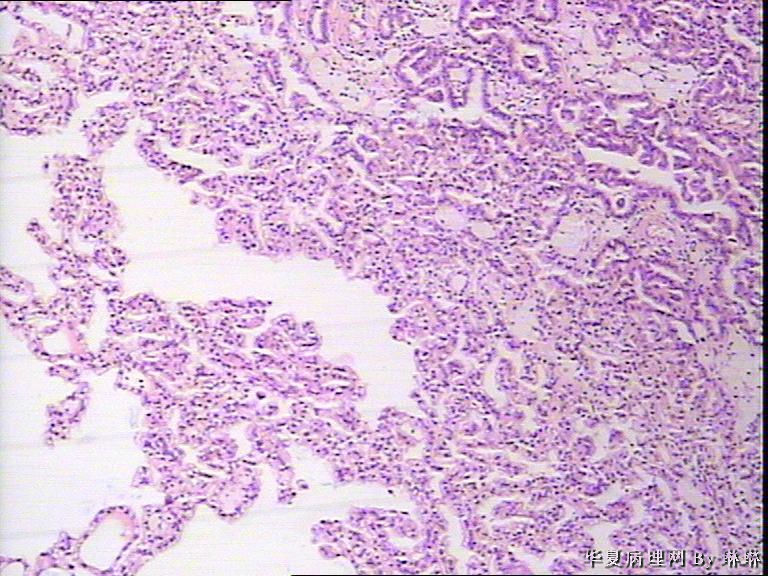

患者男性,50岁,右肾外伤可见一淡黄色圆形肿物,包膜完整,部分突出于肾表面,直径约3.5cm,切面淡黄色,质软。请各位看看,多多发表见解。

• 右肾肿瘤,请教!图3

图3

仔细看看有没有乳头状结构,要先考虑乳头状肾细胞癌,1 型。

考虑乳头状肾细胞癌

感觉还像透明细胞肾癌。

乳头状肾细胞癌